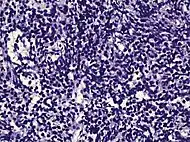

Intraductal carcinoma of the prostate with an infiltrative growth pattern may be morphologically difficult to distinguish from invasive cancer. One focus shows comedonecrosis (arrow), morphologically suggesting Gleason pattern 5 invasive carcinoma (a haematoxylin and eosin, b CK5/6)[19]

Intraductal carcinoma of the prostate with very patchy basal cells identified by immunohistochemistry. At least some of the glands lacking basal cell immunoreactivity represent intraductal rather than invasive carcinoma (a haematoxylin and eosin, b CK 5/6)[19]